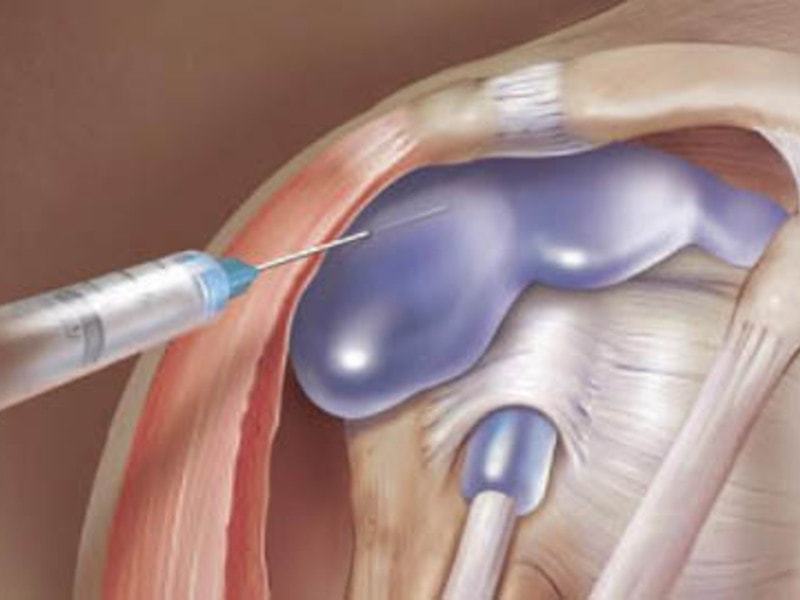

Заболевания и медицинские снимки: Жидкость в коленной чашечке

Раздел: Галерея прозрений